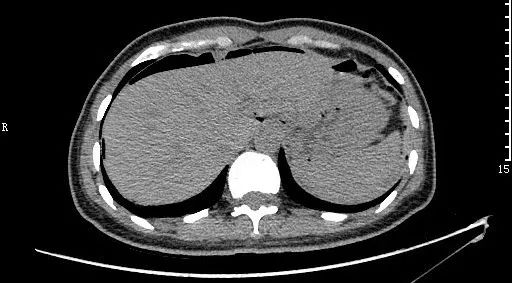

急性水肿型胰腺炎:CT平扫,胰腺明显肿胀,密度尚均匀,周围见条片渗出。

急性坏死型胰腺炎:CT平扫,胰腺密度不均匀减低,胰腺边界模糊,胰腺周围较多渗出积液,肝周可见积液。